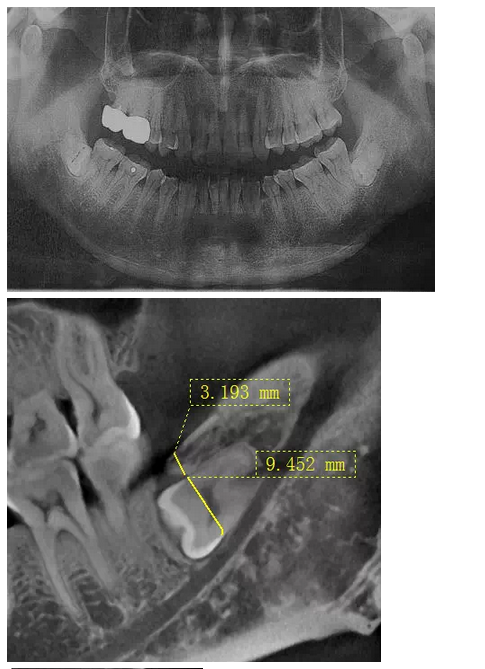

曾有這樣一位痛苦的中年患者,因雙側(cè)胸悶不適困擾二十余年,多處求醫(yī)無果,一次偶然體檢的機(jī)會,拍得口腔曲面體層片(全景片,圖一),顯示下頜雙側(cè)各有一顆水平埋伏阻生智齒,醫(yī)生建議擇期拔除。但患者更關(guān)心此二顆智齒是否是引起自己不適癥狀的原因,均被告知不敢肯定,無法從西醫(yī)角度解釋有何關(guān)聯(lián)。但痛苦驅(qū)使著患者自己去查閱了大量中醫(yī)資料,查得此下頜角處為一穴位,患者遂認(rèn)為可能是這二顆牙齒點(diǎn)中了此穴,導(dǎo)致自己胸悶不適,說服自己之后,來我院就診要求拔除。

沒有CT,在全景片上評估右下智齒與下牙槽神經(jīng)管距離很近,告知各樣風(fēng)險(xiǎn),患者表示理解并簽字。常規(guī)手術(shù)切口,翻瓣,露得一部分牙冠,去骨后,多次小心翼翼檢查車針深度,使冠根分離,去除牙冠,進(jìn)入取根階段,多次輕力試挺,均無動靜,只知牙根與下牙槽神經(jīng)管很近,卻不知具體的三維關(guān)系,所以只好小心翼翼地找間隙,此舉進(jìn)展龜速,如履薄冰,筋疲力盡,猶如兩驅(qū)小轎車行駛在泥濘的小道上,想給力卻打滑。后來還是團(tuán)隊(duì)的力量,輪番上陣,最終全部拔除,拔除后才得知原來是兩個牙根向內(nèi)直角彎曲,牢牢卡住了中間的牙槽中膈?;颊叩诙祀m然術(shù)后反應(yīng)較大,但是非常開心地告訴我們右側(cè)胸悶有明顯好轉(zhuǎn),而且右側(cè)嘴唇?jīng)]有麻木,所以要求傷口恢復(fù)好之后馬上將左側(cè)的智齒拔除。這給我們帶來了安慰的同時,也給了我們更大的挑戰(zhàn)。

在拔牙一月后,鳥槍換大炮,診所引進(jìn)了三維CT,左側(cè)智齒在拍了CT后,前后頰舌上下關(guān)系就一目了然,此牙更難拔除,因?yàn)橥耆穹▓D二),其上面覆蓋有3mm厚的牙槽骨,其下緣與下牙槽神經(jīng)管緊緊相連,較危險(xiǎn);牙冠前緣與第二磨牙遠(yuǎn)中根也緊緊相連,后緣牙根向上翹;整個牙齒偏頰側(cè),頰側(cè)皮質(zhì)骨板較厚(圖三),舌側(cè)骨板也較厚,測好牙冠頸部上下距離約為9.5mm。